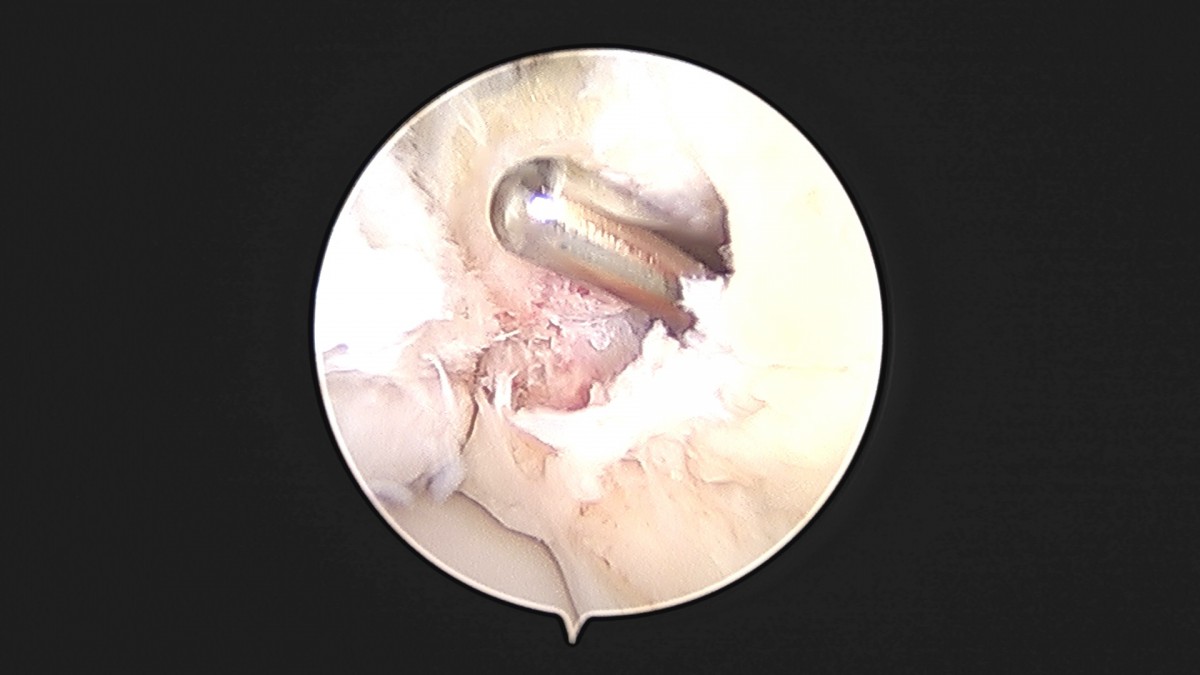

이재상원장님 발목 인대 봉합술 이주O 환자

dae765e4d9ac96aee867c9d6292d8784_1758007209_4929.jpg